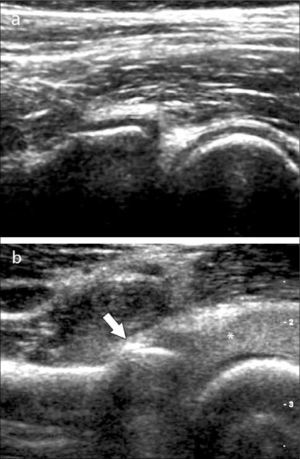

Ecografía de codoLas alteraciones más frecuentemente diagnosticadas en esta articulación son: Epicondilitis-codo del tenista (tendinopatía extensora), Epitrocleítis-epicondilitis medial- codo del golfista (tendinopatía flexora), derrame articular ya sea de origen inflamatorio o asociado a fracturas ocultas (figura 6), neuropatía cubital ya sea por atrapamiento o luxación, bursitis olecraneana (figura 7), tendinopatía tricipital, del biceps distal y su bursa, lesiones por elongación del ligamento colateral cubital, quistes/gangliones periarticulares, prominencias en rebordes óseos articulares, calcificaciones y entesopatía (14, 15).